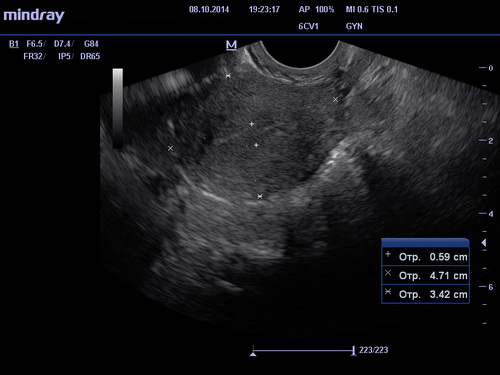

УЗИ органов малого таза

ЗаписатьсяУЗИ органов малого таза – это безопасная и безболезненная процедура обследования, обладающая высокой степенью точности и информативности, которую вы можете пройти в наших медицинских центрах. У пациентов женского пола в обследуемые органы входят матка с придатками, влагалище, передняя стенка прямой кишки и мочевой пузырь (при трансабдоминальном УЗИ). У пациентов мужчин – это предстательная железа, передняя стенка прямой кишки, семенные пузырьки и мочевой пузырь.